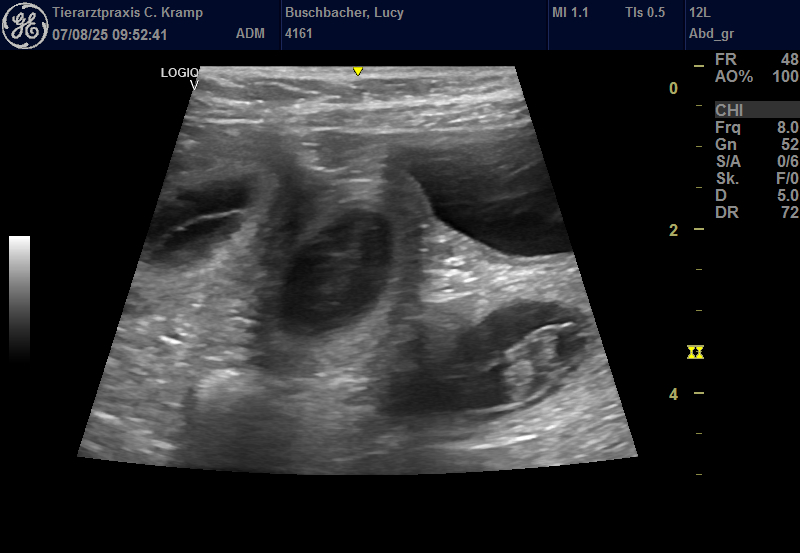

Jetzt wird’s ernst. Der Ultraschall hat gezeigt: Lucy ist trächtig! Wir freuen uns.